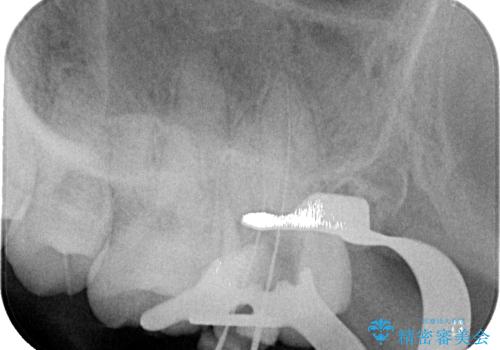

最後方歯は根管治療を行った上でオールセラミッククラウンにて補綴治療を行うこととし、手前の歯はセラミックインレーにて修復治療を行うこととしました。

当院に来院された時には既に痛みはなく、治療終了までスムーズに進めることができました。

今後は定期的にレントゲン写真を撮りながら、根管治療の経過観察を行っていくことになります。